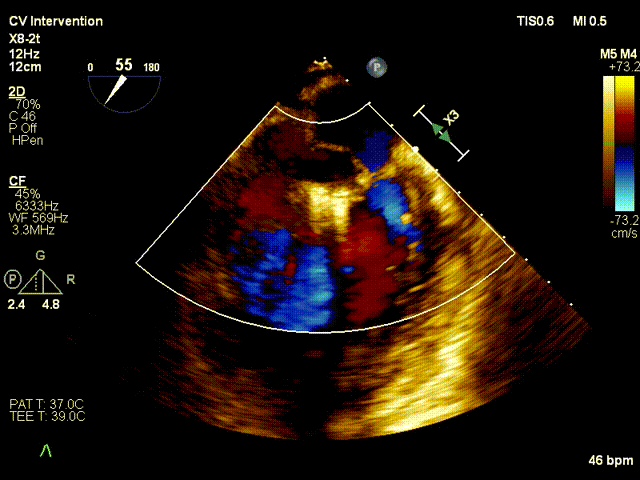

术后 commissure view 提示反流微量

术后 3D colour view